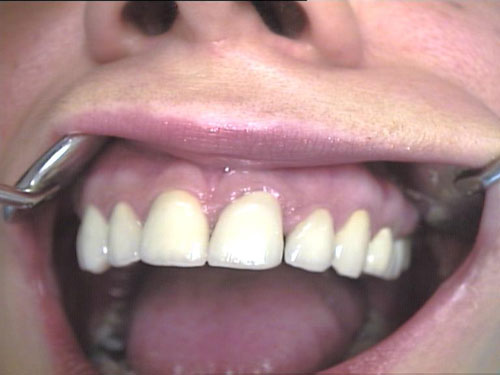

Zahn-Anomalien 2